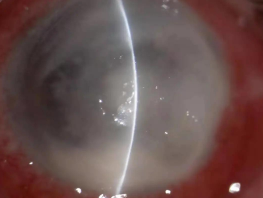

真菌性角膜炎是一種由致病真菌引起的、致盲率極高的感染性角膜病。常見(jiàn)的致病菌為曲霉菌,其次為鐮刀菌、白色念珠菌、頭芽胞菌及鏈絲菌等??沙霈F免疫環(huán)、衛星灶、偽足、菌絲苔被、前方積膿及內皮斑。